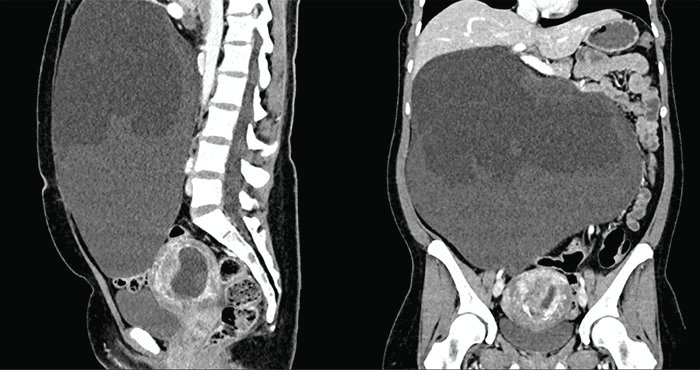

Figure 3. Preoperative CT Scan. Published with Permission

Well-defined, 16 x 20 x 30 cm cystic mass with fluid levels and no evidence of internal calcifications or fat density. The mass appears separate from adjacent organs and does not show signs of invasion

A 33-year-old woman presented after referral to the surgical oncology service at eight weeks gestational age with an incidentally found large abdominal mass on initial obstetrical ultrasound (Figure 1). Magnetic resonance imaging (MRI) of the abdomen identified a 32.5 cm x 28.1 cm x 14.1 cm mass with cystic and solid components, and internal fat, demonstrating significant mass-effect on the liver, gallbladder, inferior vena cava (IVC), bilateral kidneys, and with displacement of intestines from the right hemiabdomen into the left (Figure 2). This was her first pregnancy, and the patient described approximately one year of vague nondescript symptoms including early satiety, constipation, and weight-gain—some of which she had attributed to her pregnancy. Her family history was significant for breast cancer in a paternal aunt. Computed tomography (CT) imaging was performed due to the possibility that this retroperitoneal mass was harboring malignancy as well as for preoperative planning. Imaging showed a large, well-circumscribed 16 x 20 x 30 cm cystic mass containing fluid levels, with a separate 2.4 x 1.0 cm well-circumscribed mass along the celiac axis, without evidence of metastasis or obvious invasion (Figure 3). No specific tumor markers were obtained. Due to concern for malignancy and worsening mass-effect on intraabdominal organs in the setting of viable intrauterine pregnancy, the decision was made to proceed with surgical resection prior to the second trimester.

Ultrasound is often the initial modality used in diagnosis, as it can be used to differentiate between solid and cystic components and may be able to detect calcification from teeth and/or bone, or posterior sound attenuation from sebaceous material and hair within a cyst cavity.4,5 It can be difficult to determine the true location of masses by ultrasound alone, specifically while differentiating between ovarian and retroperitoneal tumors.10 Further imaging with computed tomography (CT) or magnetic resonance imaging (MRI) is often needed for diagnosis and to determine potential malignancy.5,8,10 MRI was performed in our patient to initially characterize the mass,  and CT imaging was employed to further evaluate potential malignancy and preoperative planning. Characteristic findings on CT imaging include well-marginated, multilobulated complex masses with both cystic and solid components; and fluid, fat, soft tissue, and bone densities observed in the retroperitoneal space. The presence of hypoattenuating fat within the cyst or calcifications in the cyst wall is highly suggestive of cystic teratoma.5,10 Our patient's CT imaging demonstrated a large 16 x 20 x 30 cm well-circumscribed cystic mass with fluid levels, without internal calcifications or fat density identified, that did not appear to arise from adjacent organs or demonstrate invasion and was concerning for mesenteric lymphangioma per radiology review (Figure 3). The second 2.4 cm x 1.0 cm mass was well-circumscribed and appeared to contain proteinaceous or hemorrhagic material. Absence of mature tissues, sebum, and occurrence in childhood years have been reported to be predictors of malignant change.5 MRI has been used, specifically during pregnancy, to avoid radiation exposure, as these lesions have a high fat content and appear hyperintense on T1-weighted images.5,8 The MRI performed on our patient demonstrated a 32.5 x 28.1 x 14.1 cm arising from or abutting the inferior surface of the liver, with both cystic and solid components with evidence of internal fat, with differential diagnosis considering fibrolamellar hepatocellular carcinoma, hepatic adenoma, giant hemangioma, leiomyosarcoma of the mesentery, or a cystic teratoma per radiology report (Figure 2).